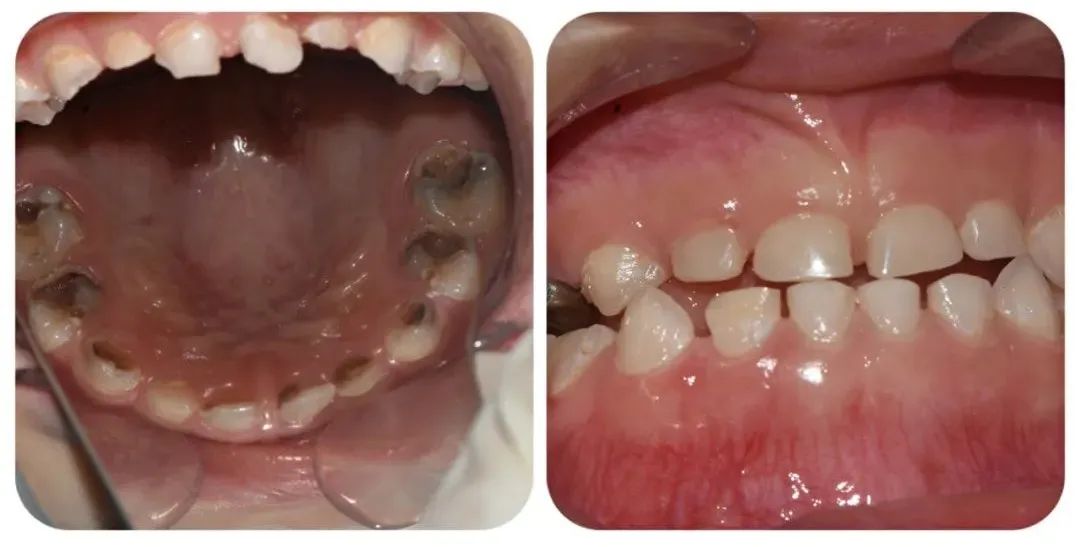

術(shù)中,口腔科主任毛亮與主治醫(yī)師王文涵,在麻醉科醫(yī)護(hù)人員的配合下進(jìn)行手術(shù)。華華在“睡覺”過程中,全程嚴(yán)格監(jiān)控,根據(jù)個(gè)體情況和手術(shù)進(jìn)程,調(diào)整用藥用量,保障手術(shù)安全。歷時(shí)2小時(shí),一次性完成了對(duì)患者多生牙、齲齒、牙髓疾病,殘根及殘冠等患牙的治療。

(修復(fù)前后對(duì)比)